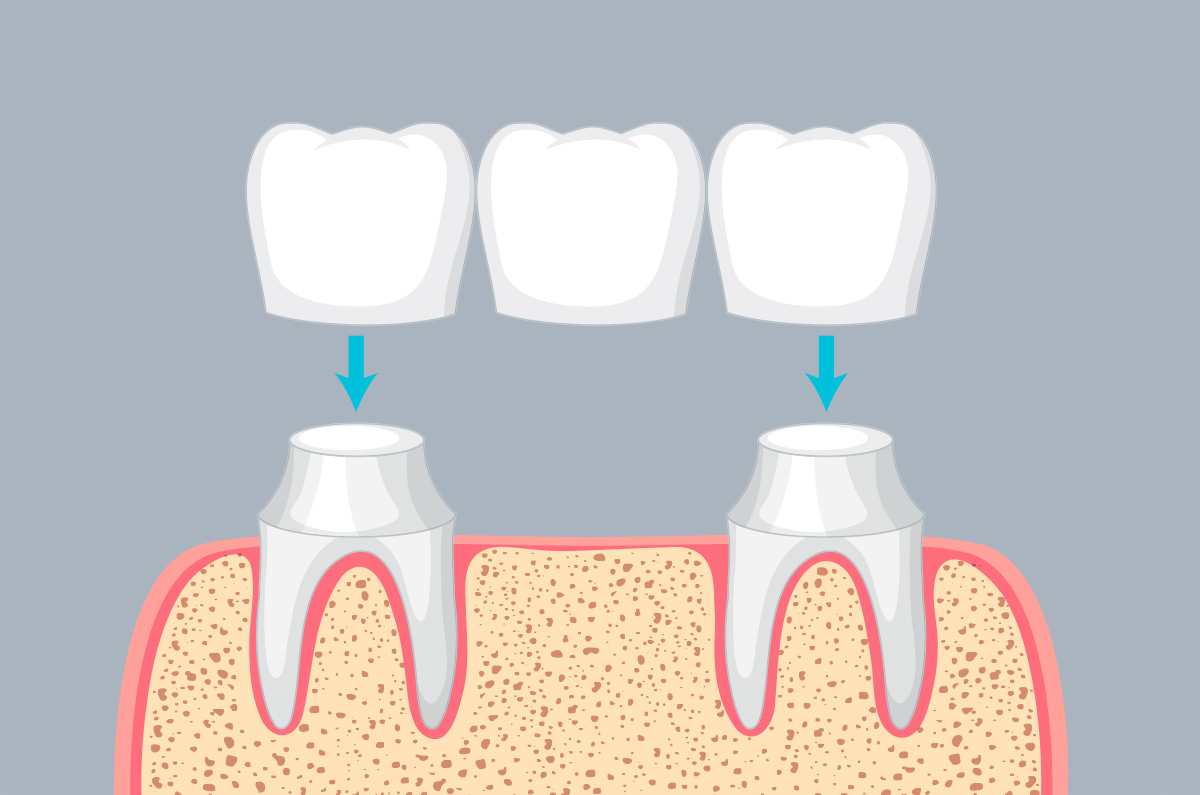

Amor Dental by Dr. Lorna M. Quimco offers premier dental services at affordable rates, including veneers, bridges, whitening, implants, TMJ therapy, braces, and dentures. Established in 1999, our goal is to provide top-notch dental care for confident smiles. Dr. Quimco, with over 25 years of experience, is renowned for her expertise in cosmetic dentistry. She graduated from Cebu Doctors University and pursued postgraduate studies at the Philippine Academy of Esthetic Dentistry, excelling in Dental Implantology under Dr. Hom-Lay Wang at the University of Michigan.

She practices Biomimetic Dentistry, focusing on preserving tooth structure by replicating natural tissues. She also specializes in Neuro-Muscular Dentistry, employing advanced techniques for personalized treatment plans. Committed to continuous learning, she travels globally for the latest innovations.